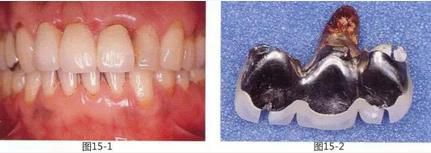

圖15-5  橋體部增大的同時通過APF將鄰接牙牙周袋去除。同時進行上唇系帶的切除。

圖15-6  治愈期間對臨時修復體進行形態(tài)修整。